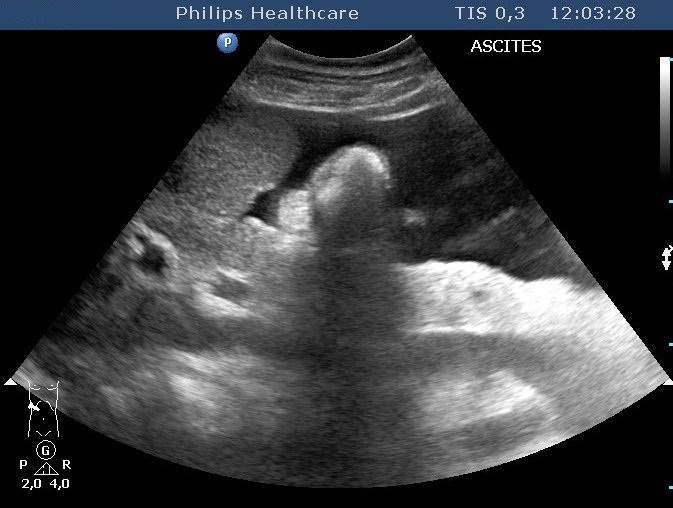

No direct association among the extent of fibrosis, the degree of the dysfunction and the ultrasound morphology was detected, normal liver structure can be observed in case of an extended encephalopathy as well. The right lobe size can decrease, left lobe and caudate lobe hypertrophy develops. Lateral segment of the left lobe can increase besides the decrease of the medial segment's size. The fibrosis itself does not change the parenchyma reflectivity. Increased reflection can be observed if it accompanies with fat deposition as well. On the other hand, rough echostructure, inhomogenecity can be observed in the parenchyma due to the miliary (4-5 mm or smaller) regenerative nodules. Bigger nodules result extensive surface incongruences (Figure 14).

Figure 14: Liver chirrosis, nodular surface, ascites

The regenerative nodules can appear as moderately hypoechoic lesions, mimicing hepatocellular carcinoma which develops more frequently based on cirrhosis related to B and C viral hepatitis. The nature of the developing nodule can only be clarified by biopsy in some cases. Small amount of free abdominal fluid (ascites) can be imaged well by US. Signs of portal hypertension can be also recognised very well, however, the exact determination of the circulation statuses goes over the possibilities of the rutine US examination obviously. In this case, an accessory color duplex US examination using an appropriate top category device is necessary.